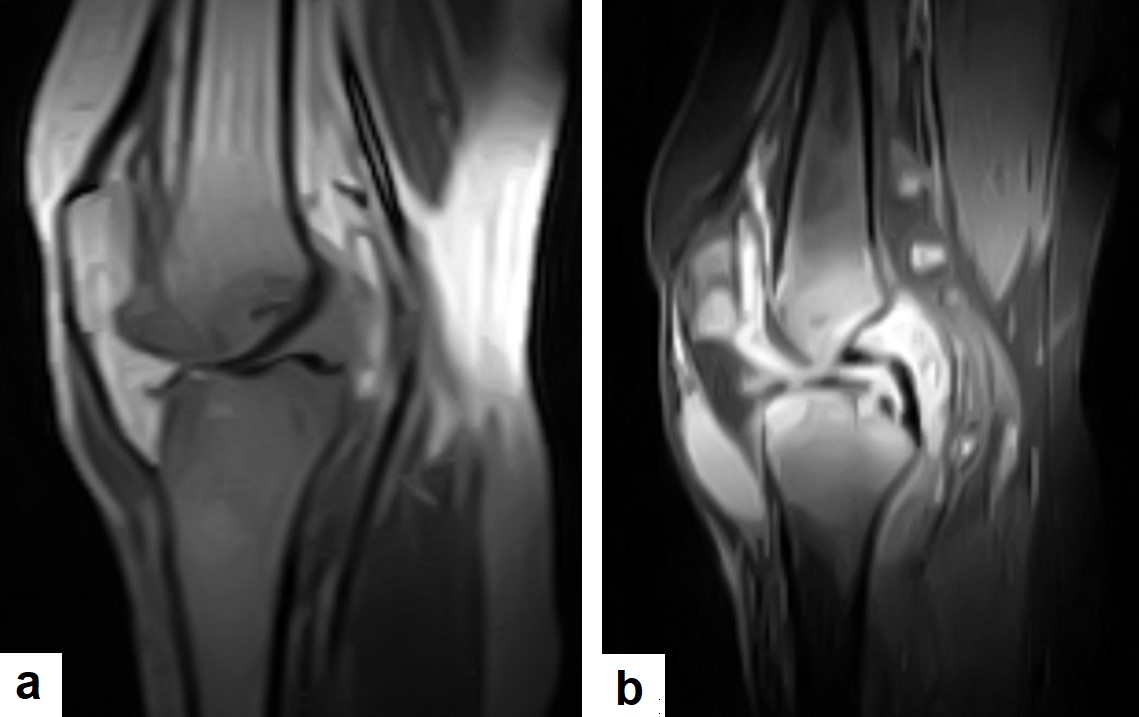

TB can affect any part of the MSK system, and symptoms of TB may be insidious, causing TB not to be considered. CT and MRI imaging modalities can bring suspicion to TB diagnosis [19]. MSK TB is a differential diagnosis of a wide range of bone lesions. High suspcion of TB is required, and a final diagnosis of TB can be carried out by using culture; in addition, a synovial biopsy may be needed [20] (Figure 24).

Figure 24. Knee TB in a 45-year-old patient with proved case of knee TB infection. Selected sagittal MRI images of (a) T1-weighted image and (b) T2-weighted image show extensive oedema of the articular surfaces of the knee, appearing as low signal intensity on T1 and high signal intensity on T2 with diffuse synovial thickening and large bone erosions (arrow heads), with mild joint effusion and a prepatellar pocket of fluid collection, which appear as low signal intensity on T1 and high signal intensity on T2. In addition, multiple enlarged popliteal lymph nodes were present.